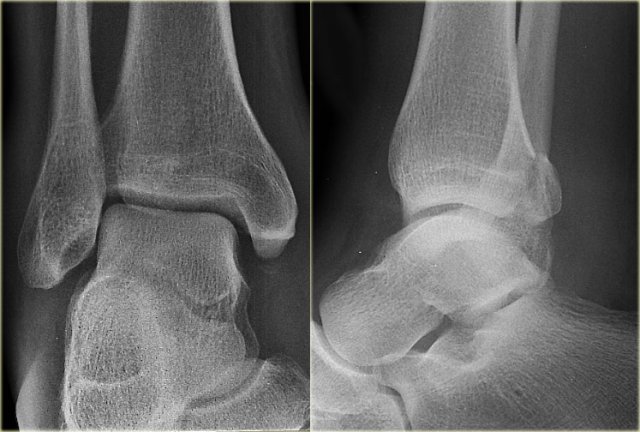

Example 2

• First impression

There is a fracture of the posterior malleolus.

Classification according to Weber is not possible.

An isolated fracture of the posterior malleolus is uncommon, but as part of a supination exorotation (Weber B) or pronation exorotation injury (Weber C) it is quite common.

So we have to re-examine the films to look for signs of a Weber B or C fracture.

• Re-examination

No sign of an oblique fracture of the lateral malleolus, so we can exclude a Weber B fracture.

There is still the possibility of a Weber C fracture, i.e. medial rupture or avulsion, high fibular fracture and finally a posterior malleolar fracture.

Now we notice the subtle avulsion of the medial malleolus (red arrow).

Additional radiographs of the lower extremity demonstrate a high fibular fracture (blue arrow).

• Final report

Weber C stage 4.